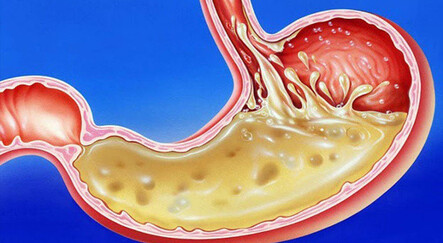

Her 10 kişiden 3’ünün çektiği reflü eziyeti, diyet ve ilaç tedavisi ile iyileşmediği durumlarda cerrahi yöntemler devreye giriyor. Kapalı yöntemle yapılan ameliyatsız operasyonlar uygun hastalarda neredeyse tam şifa getiriyor.

ZİYNETİ KOCABIYIK'IN HABERİ -Reflü toplumda en sık görülen hastalıkların başında geliyor. Günümüzde her 10 kişiden iki ya da üçü mide reflüsüyle baş etmeye çalışıyor. Fakat “midedeki asidin yemek borusuna doğru kaçması” olarak tarif edilen reflü şikâyetlerinin diyet ve ilaç tedavisi ile iyileşmediği durumlarda kapalı yöntemle yapılan operasyonların yüz güldürücü sonuçlar verdiğini söyleyen Türk Gastroenteroloji Derneği İkinci Başkanı Prof. Dr. Müjde Soytürk, “Cerrahi etkilidir ancak komplikasyon riski, maliyetinin yüksek oluşu, ameliyat sonrasında yutma güçlüğü, geğirememe, artmış gaz ve şişkinlik gibi yakınmaların ortaya çıkması gibi olumsuz yönleri vardır. Son yıllarda giderek artan endoskopik tedavi seçenekleri hastalar için daha az riskle oldukça yüksek başarıya sahip tedavi imkânı sağlıyor” dedi.

Hastaların hayat kalitesini olumsuz yönde etkileyen bir hastalık olduğu için reflü tedavisinin önemli olduğuna işaret eden Prof. Dr. Soytürk, “Reflü hastalığında görülen ana şikâyetlerden birincisi mideden yukarıya doğru göğüs kemiği arkasında hissedilen yanma, ekşime, ağrı ve rahatsızlıktır. Diğer ana şikâyet ise ağza acı ekşi su ya da yediklerinin gelmesidir. Her reflü hastasında illa bu iki şikâyetin birlikte bulunması gerekmez. Bazı hastalarda sadece biri görülür. Bunların dışında reflüde geğirme, ses kısıklığı, kuru öksürük, hıçkırık, bulantı, kusma, horlama, dişlerde yıpranma gibi çok sayıda rahatsız edici yakınma ortaya çıkabilmektedir” şeklinde konuştu.